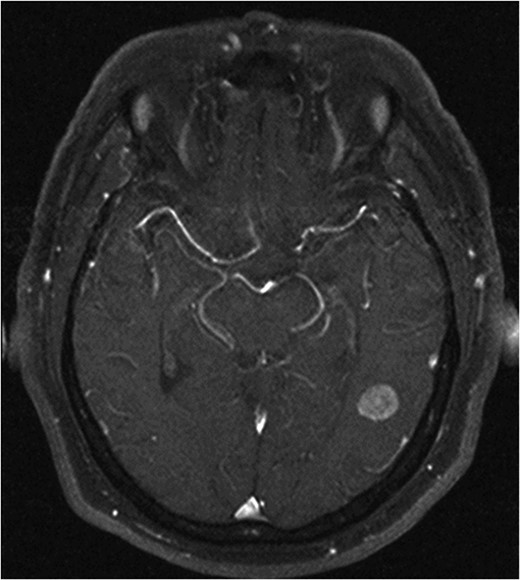

He made an uneventful recovery but presented 1 year later with intermittent dysphasia and confusion. MRI of the brain revealed a homogeneously enhancing lesion in the left posterior temporal lobe (Fig. 1). Staging CT scans identified no other lesions and this was felt to be an isolated metastasis. The patient had a craniotomy and excision of the tumour. Histopathology confirmed a high-grade neuroendocrine carcinoma with an identical immunohistochemical profile consistent with metastatic Merkel cell carcinoma (Fig. 2).

Axial T1 with Gadolinium MRI showing no evidence of recurrence at 10-year follow-up.